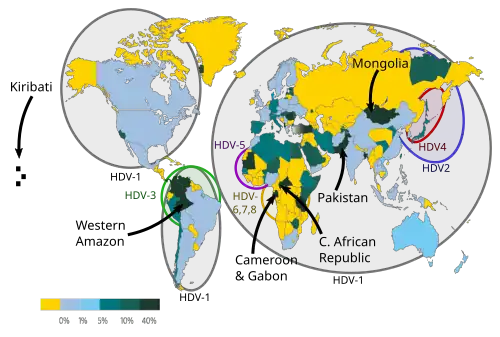

Author: Mario Rizzetto

Hepatitis D is a globally occurring liver disease. It afflicts those who have been infected by both the Hepatitis B virus (HBV) and also the Hepatitis D virus (HDV), since HDV needs the hepatitis B surface antigen (HBsAg) to replicate. It is therefore most prevalent in countries where HBV infection is also common, currently the Amazon basin and low income regions of Asia and Africa. Improved measures to control HBV in industrialised countries (such as by vaccination) have also reduced the prevalence of HDV, with the main remaining at-risk populations in those countries being injection drug users and immigrants from endemic HDV areas.